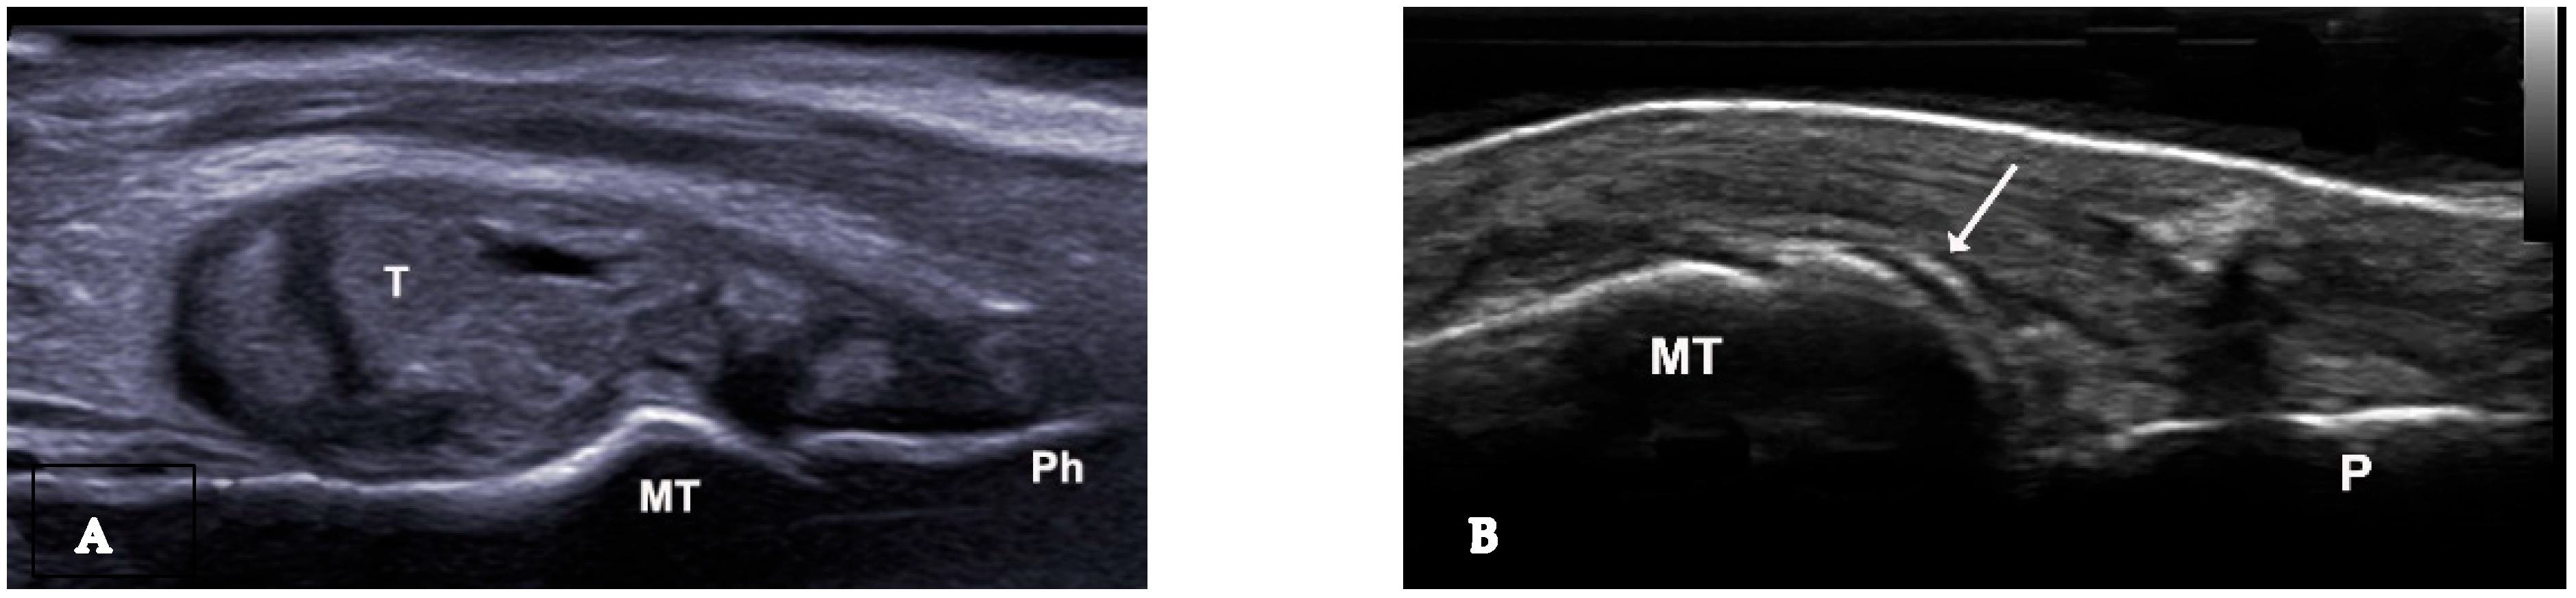

Figure 1.

Baker cyst in transverse (A) and longitudinal (B) view with the presence of multiple hyperechoic spots “snowstorm sign”.

Figure 2.

(A). Urate deposits, grade 3 (definite and severe) visible in longitudinal view at the first metatarsophalangeal joint. (B). Urate deposits at de surface of the metatarsal bone cartilage—double contour sign. MT—metatarsal bone, P—phalanx, T—intraarticular tophus, arrow—double contour sign.